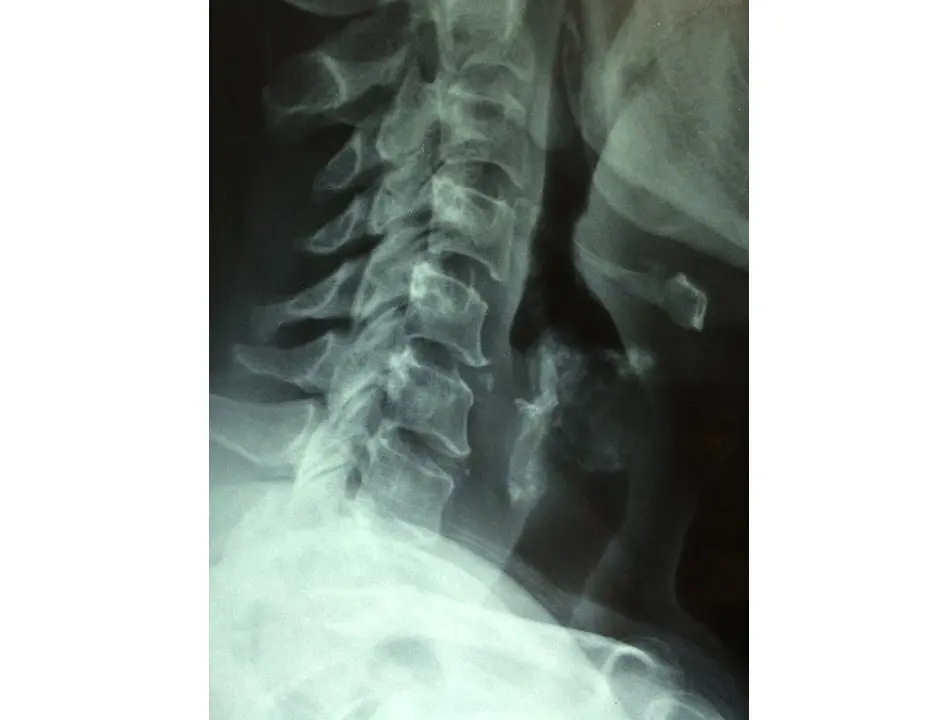

La realización de seis intervenciones quirúrgicas en directo atraerán a Santander a un millar de especialistas en oncología radioterápica, que participarán en la 19 edición del Congreso de la Sociedad Española de Oncología Radioterápica (SEOR) que se celebrará entre el 8 y el 10 de junio en el Palacio de Exposiciones. Esta edición congregará al mayor número de especialistas de 19 citas celebradas hasta el momento debido a la "importante novedad" de las operaciones en directo, que se realizarán en dos quirófanos instalados en el Palacio de Exposiciones gracias a las dotaciones y especialistas con que cuenta el Hospital Universitario Marqués de Valdecilla (HUMV), el Hospital Virtual Valdecilla (HvV) y su instituto de investigación, el IDIVAL. Así lo ha avanzado el jefe del Servicio de Oncología Radioterápica de Valdecilla, Pedro Prada, que este miércoles ha presentado el 19 Congreso de la SEOR, y el primero de la Sociedad Española de Oncología Clínica (SEOC), en una rueda de prensa junto a la alcaldesa de Santander, Gema Igual, y la concejala de Turismo, Miriam Díaz. Prada ha destacado que las operaciones en directo "es algo que nunca se ha hecho y posiblemente no se pueda volver a repetir" en este Congreso ya que sólo es posible gracias a los equipamientos tecnológicos y la especialización que hay en Valdecilla, que ha enfatizado que cada año recibe a pacientes de todas las Comunidades Autónomas para realizarse estas intervenciones e imparte cursos a especialistas de otros hospitales. Ha indicado que, a pesar de que al congreso asistirán un millar de especialistas, obviamente se ha tenido que limitar el número de asistentes a las intervenciones que se realizarán en directo a unos 60 por operación y también ha avanzado que éstas serán radioterápica intraoperatoria de cáncer de próstata, de máma, de cervix, de páncreas y ocular. Plaza, que encabeza el comité organizador del Congreso, ha ensalzado que estas intervenciones en estos dos quirófanos, que se instalarán en dos salas del Palacio de Exposiciones, permitirán mostrar las innovaciones de Valdecilla en esta especialidad, así como la preparación de sus profesionales, y permitirán a los asistentes conocer el trabajo que se hace en el hospital cántabro. El Congreso, al que asistirán especialistas de diferentes puntos de España y Europa pero también de Estados Unidos, ha indicado que contará, como es habitual, con ponencias, comunicaciones, mesas redondas y debates, así como una zona de stands de empresa privadas y farmacéuticas. Por su parte, la alcaldesa de Santander ha destacado la importancia que tiene para Valdecilla este congreso, en el que mostrará su trabajo en una especialidad, la de oncología radioterápica, en la que es "puntera", así como el buen hacer de sus profesionales. También ha ensalzado la importancia de esta cita para la ciudad, ya que la asistencia de un millar de personas supondrá un impacto económico en los hoteles y los restaurantes, así como en empresas de organización de eventos o en el sector del taxi. Así, ha apuntado que la media de gasto de un congresista en la ciudad es algo más de 200 euros por día. En este sentido, ha apuntado que, entre el 1 y el 11 de junio, hay múltiples eventos deportivos programados en la ciudad y muchos congresos y reuniones de entidades y colectivos nacionales e internacionales que, en su conjunto, reunirán esos días en Santander a unas 5.300 personas.